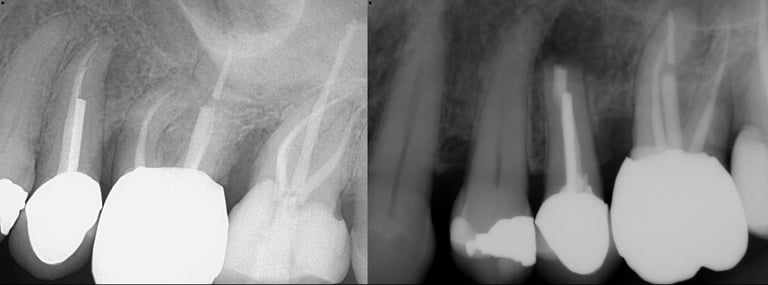

Gallery 2: Retreatment Cases

Retreatment Root Canal Cases with preoperative and postoperative radiographs.

#10 ReTx (original RCT poorly done)

#30 ReTx (original RCT had missed canal)

#14 ReTx (original RCT had missed 4th canal)

#19 ReTx (original had missed canal)